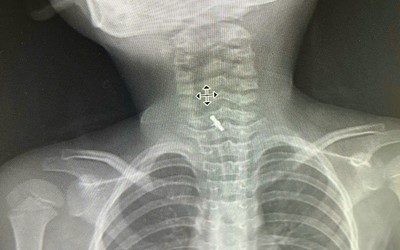

Chụp X-quang họng bé trai 7 tháng tuổi, bác sĩ sốc nặng khi phát hiện "bí mật" đáng sợ

Các bác sĩ đã lấy chiếc ghim ra khỏi cổ họng bé trai 7 tháng tuổi một cách an toàn sau khi em vô tình nuốt phải nó.